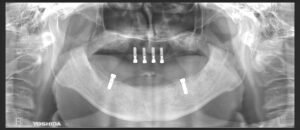

レントゲン写真上でも全顎的に重度の歯周病と診断して、IOD治療を選択されました。

残存歯を抜歯後、上顎は4本、下顎は2本インプラントを埋入しました。

インプラントが顎骨と結合した後、IODを作成しました。